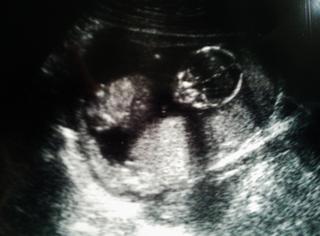

Inak na som sa ani nepochválila...minulý týźdeň sme boli aj na prejasnení , takže výsledky v norme a malinké má už 9 cm...teda ...a keby ste videli čo vyvádzalo...najprv len klasický prštek v puse, potom sa akosi prekrútilo do sviečky a kopalo o 106, potom sme videli ako prehĺta plodovú vodu a nakoniec začalo čkať...no s mužom sme sa nasmiali, doktor mal problém namerať to prejasnenie NT. ...no krásny zážitok 🙂 fakt...teraz voláme malinké " náš krásny mimozemšťan" , veď posúďte sami 🙂